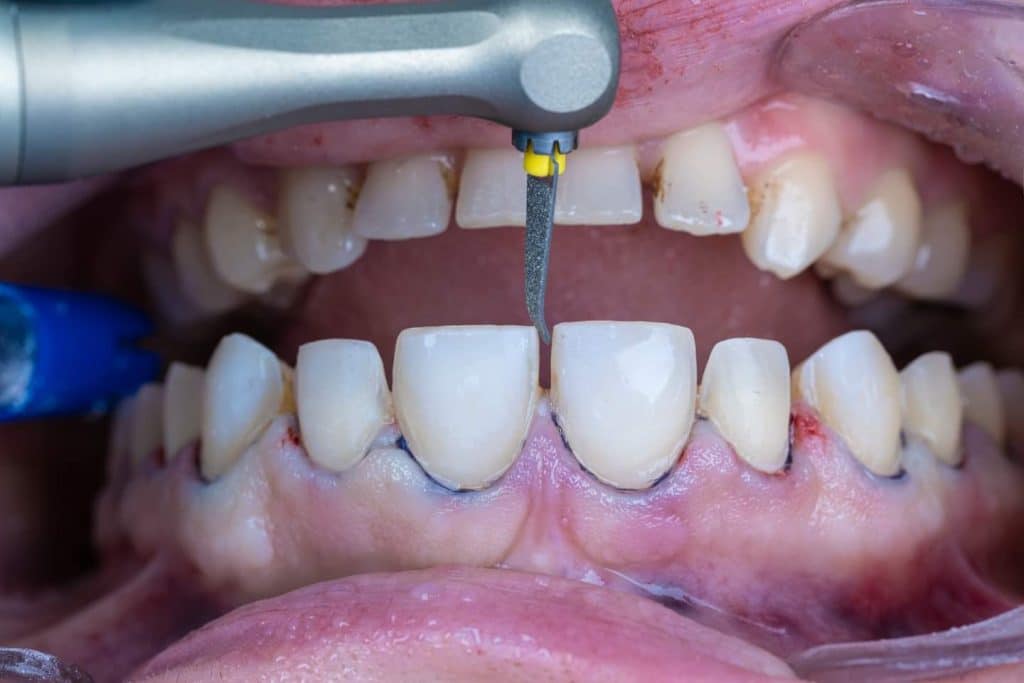

The case presented in this case report is for a 27-years-old female patient with a chief complaint of aesthetic correction for her smile. The patient was unhappy with her smile. After clinical examination, there were previous old composite veneering done poorly and incorrectly to close the multiple interdental spacing. After discussing the various treatment options (i.e., orthodontic treatment, direct, or indirect veneers), indirect ceramic veneering was selected. The step-by-step treatment protocol is presented in the images below.